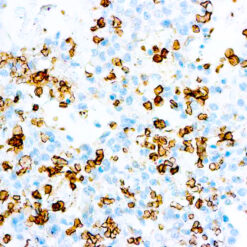

CD79a Antigen (HM47/A9)

This antibody is specific to human CD79a antigen complex, consisting of two polypeptides non-covalently associated with membrane-bound immunoglobulins on B cells. This complex of polypeptide and immunoglobulins constitute the B cell antigen receptor. The two components of this complex are designated CD79a and CD79b. The CD79a antigen appears at the pre-B cell stage, early in maturation and persists until the plasma cell stage. The CD79a antigen is found in majority of acute leukemias of precursor B cell type, in B cell lines and B cell lymphomas.

| Positive Control Tissue | Tonsil |